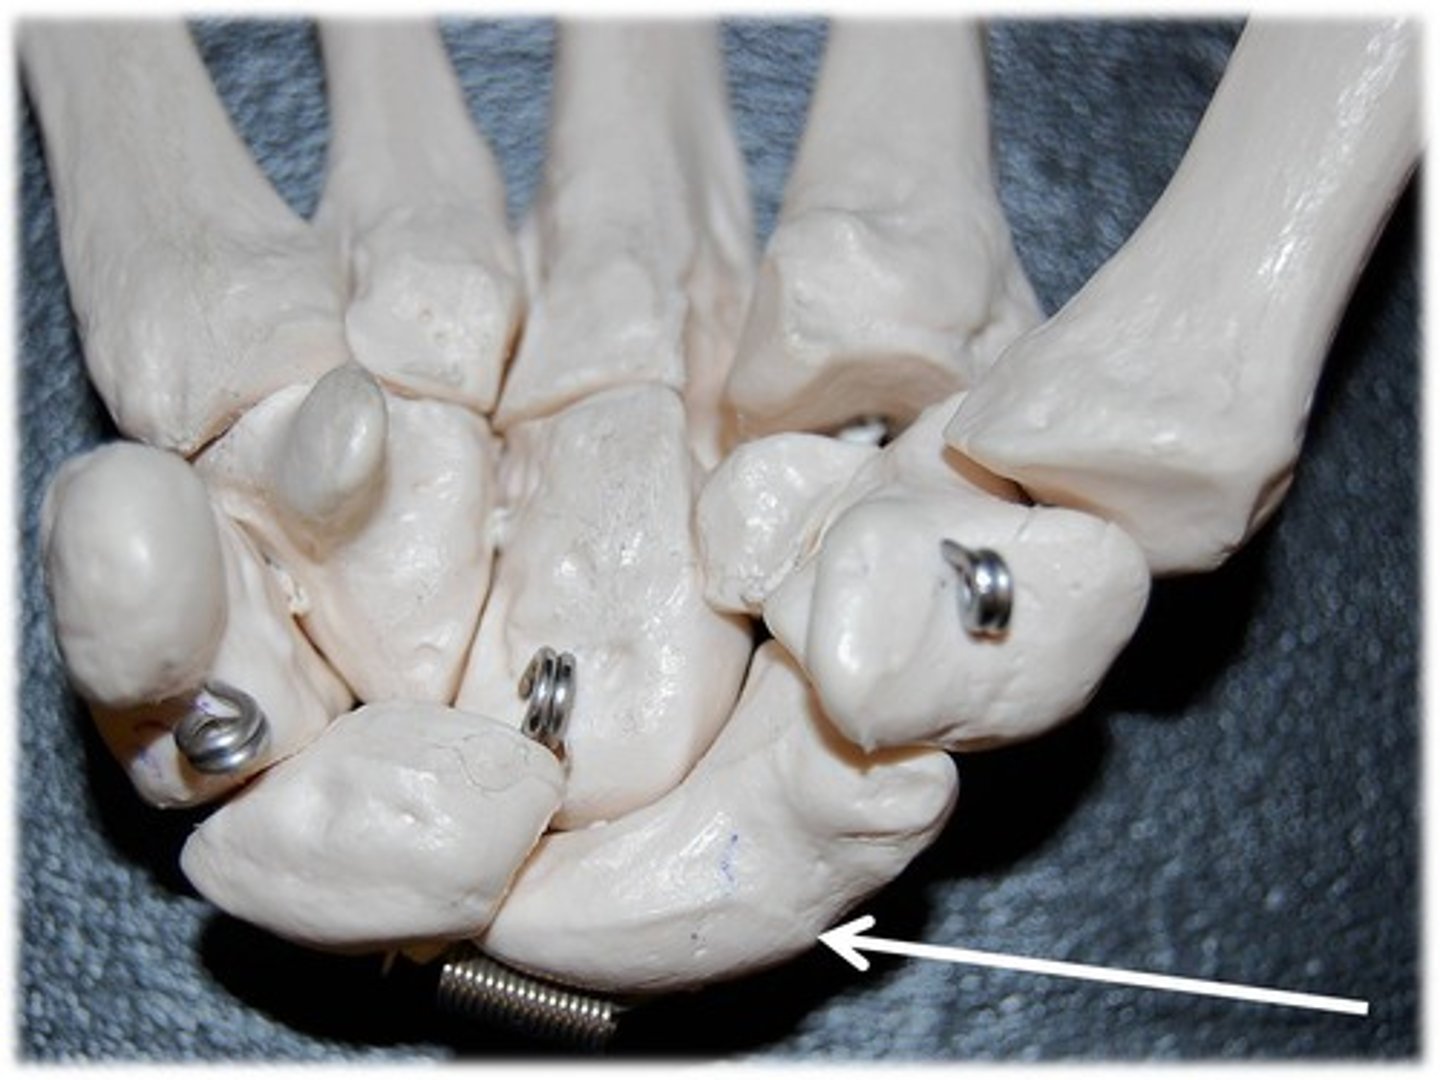

metacarpals

1st metacarpal

ID bone

1st proximal phalanx

ID bone

4th proximal phalanx

ID bone

4th metacarple

ID bone

carpals

ID group

hamate

ID bone

1st metacarple

ID bone

metacarpals

ID bone group

carpals

ID bone group

phalanges

ID bone group

metacarpal

ID YELLOW bones

carpals

ID PURPLE bones